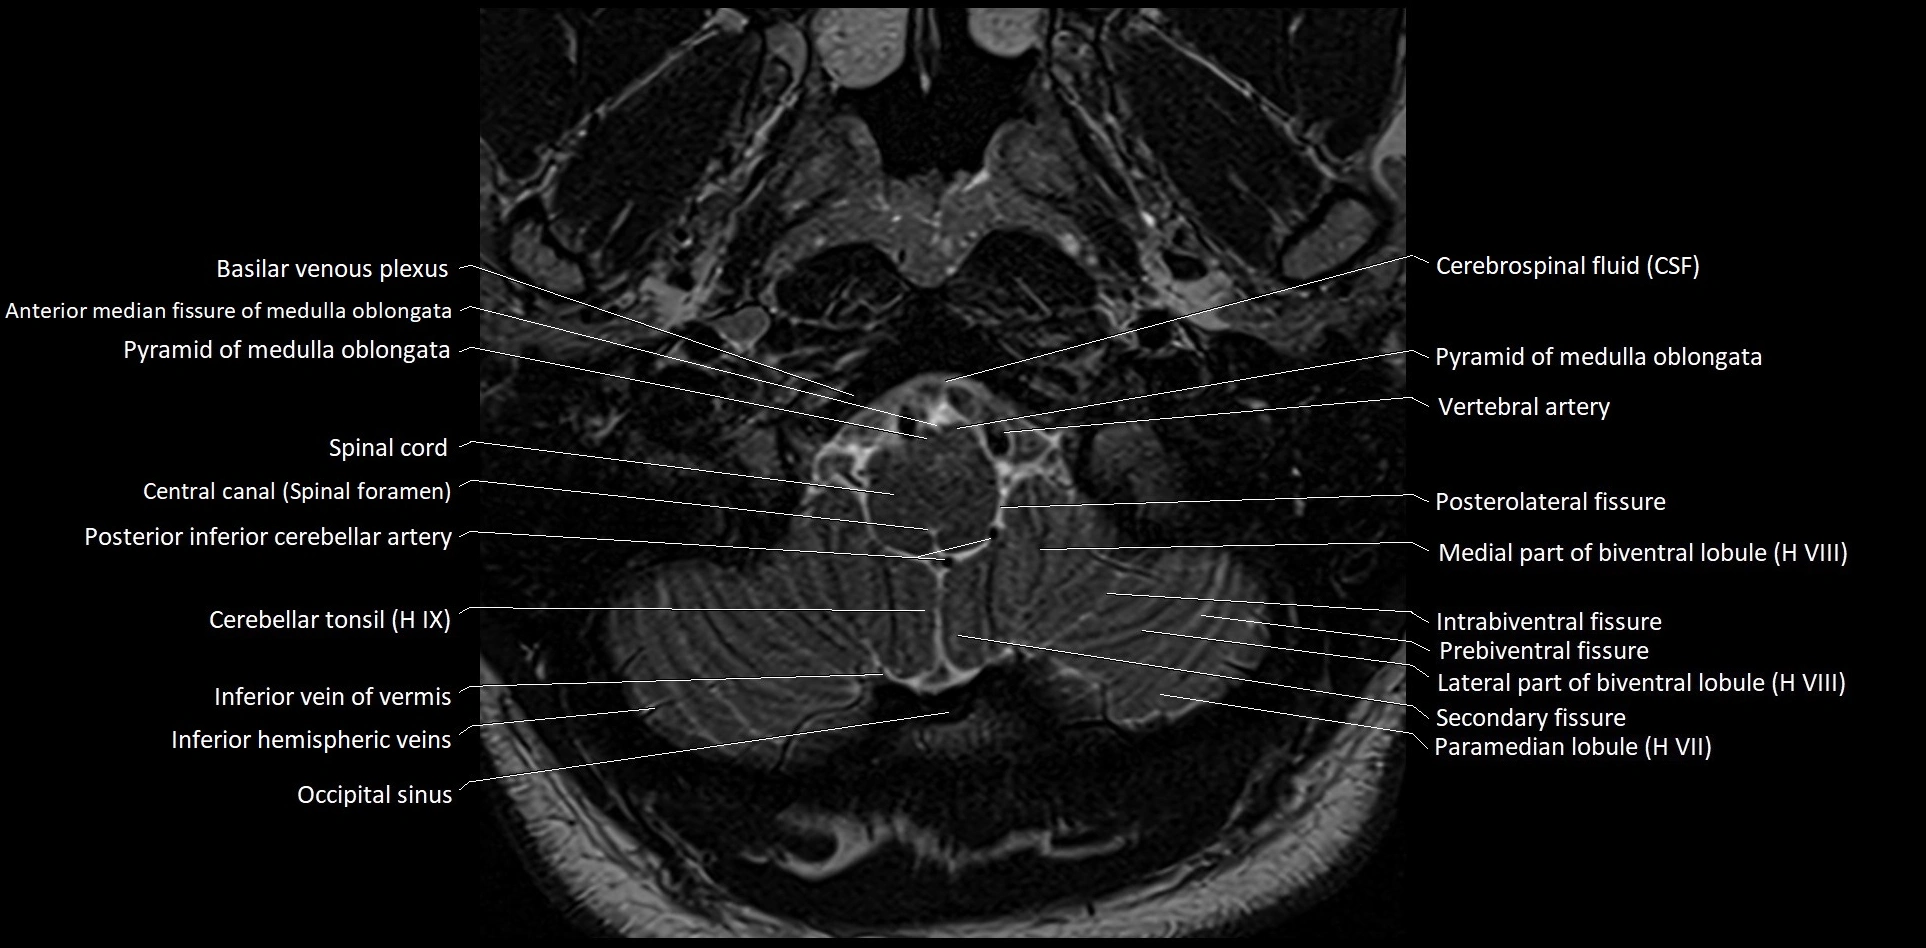

MRI images